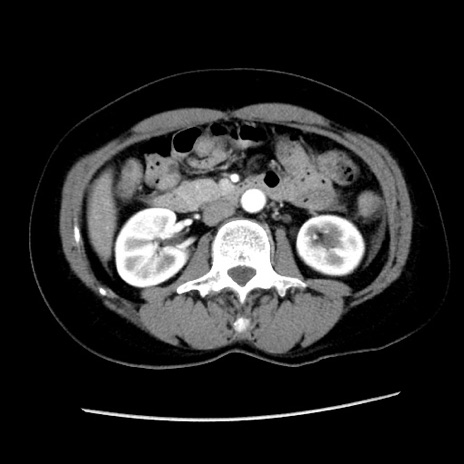

冠状断像